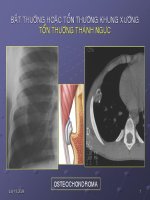

Tổn thương thành ngực potx